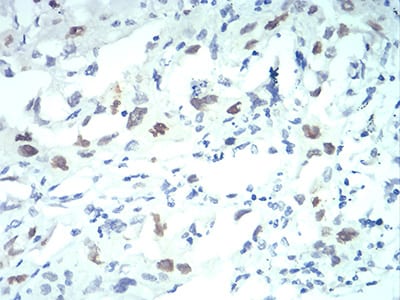

| IHC | 1/200 - 1/1000 | Human,Mouse,Rat |

**摘要**: 本研究通过免疫组化(使用KPNA2抗体)发现KPNA2在肺腺癌组织中高表达,其表达水平与患者预后不良相关。实验表明KPNA2通过促进STAT3信号通路激活驱动肿瘤转移,抗体检测结果支持其作为潜在治疗靶点。

**摘要**: 通过对比分析肝癌组织与正常肝组织的KPNA2抗体染色结果,发现KPNA2在早期肝细胞癌中特异性高表达,其敏感性和特异性优于传统标志物AFP,提示其作为早期诊断生物标志物的潜力。

KPNA2 (Karyopherin Alpha 2), also known as importin subunit alpha-1. is a member of the importin α family responsible for nucleocytoplasmic transport. It facilitates the nuclear import of proteins containing classical nuclear localization signals (NLS) by forming a heterodimeric complex with importin β1. KPNA2 plays critical roles in regulating cell cycle progression, gene expression, and signal transduction by mediating the nuclear transport of transcription factors (e.g., p53. c-Myc) and other cargo proteins. Its expression is tightly controlled during normal cellular processes but is frequently dysregulated in cancers. Overexpression of KPNA2 has been linked to tumorigenesis, metastasis, and poor prognosis in multiple cancers, including breast, lung, ovarian, and hepatocellular carcinomas, making it a potential oncogenic biomarker and therapeutic target.

KPNA2 antibodies are widely used in research to detect protein expression, localization, and interactions. They enable applications such as Western blotting, immunohistochemistry, immunofluorescence, and co-immunoprecipitation. These antibodies help elucidate KPNA2's role in disease mechanisms, particularly its involvement in cancer progression through aberrant nuclear transport of oncoproteins. Recent studies also explore KPNA2's relevance in viral infections, neurodegenerative diseases, and autoimmune disorders. Commercial KPNA2 antibodies are typically developed against specific epitopes, with validation across species and sample types. Researchers must verify antibody specificity using knockout controls due to homology among importin α isoforms. As interest grows in targeting nuclear transport pathways for therapy, KPNA2 antibodies remain vital tools for diagnostic and functional studies.